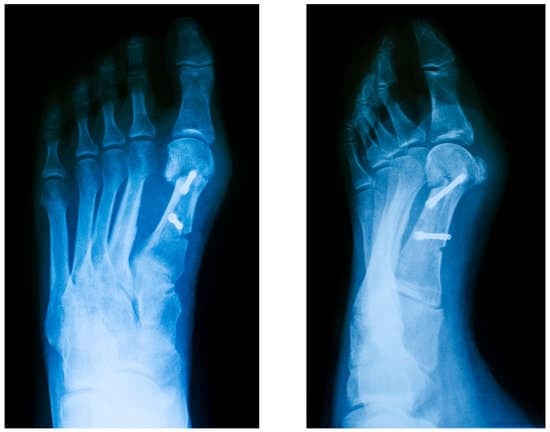

관절 유합술

관절 유합술은 발가락 관절을 고정하여 변형을 교정하는 수술입니다. 이 방법은 관절염이 동반된 경우나 변형이 매우 심한 경우에 사용됩니다.

방법:

변형된 관절을 제거합니다.

뼈를 올바른 위치로 정렬합니다.

나사와 판을 사용하여 관절을 고정합니다.